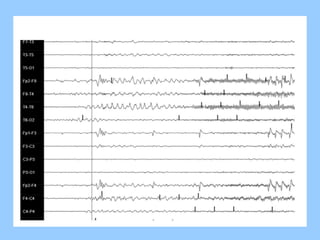

1. The document discusses EEG patterns and findings in various neurological conditions seen in children. It includes descriptions of normal EEG findings as well as abnormal patterns seen in conditions like absence seizures, West syndrome, benign childhood epilepsy with centrotemporal spikes, Lennox-Gastaut syndrome, non-convulsive status epilepticus, subacute sclerosing panencephalitis, and herpes encephalitis.

2. Case studies are presented with clinical histories and EEG findings to illustrate different pathologies. Treatment options are also mentioned for many of the conditions.